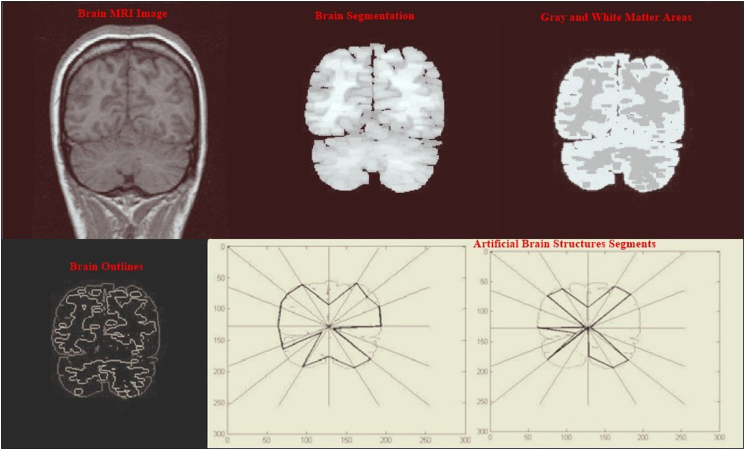

The new approach of measuring BPB for early AD detection is based on designing the brain biometrics computerized intervention system (BBCIS) (Fig. 1), which will be conducted on suspected AD patients with early cognitive signs. The construction of BBCIS includes eight phases as follows: the 1st and 2nd phases depend on creating a secret key and ID for the purpose of authentication/identification of each enrolled patient, followed by the acquisition of brain images performed by sMRI (phases 1 and 2) (Fig. 1, Fig. 2). The 3rd phase includes the acquisition of EEG brain wave signals and their integration with simultaneous sMRI imaging (Fig. 2, Fig. 3). The next two phases (4 and 5) include respective brain image slicing, segmentation, and analysis of extracted features (volume, surface and boundaries) (Fig. 4). While the 7th phase includes creating computerized artificial brain transformation and coordination analysis and then storing the data/geographical changes under the previously identified secret ID key assigned to each enrolled patient for the eight assessed phases (Fig. 2, Fig. 3, Fig. 4). Concerning the last phase, which mainly depends on raw data imaging and the analysis of brain waves, the degree of association depends on using preprocessing, extraction, and sequencing tools along with the appropriate use of ROC curve to avoid high image false-positive results (Fig. 4). In contrast, routine sMRI and EEG will be conducted weekly on the suspected AD subjects at certain fixed time intervals in order to detect morphological brain changes from one week to another.

Fig. 4.

Illustration of obtained BPB images and results that can be used in early AD detection.